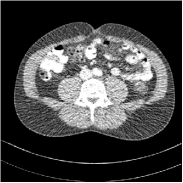

Fig. 3 illustrates the image evolution over SUPER layers (i.e., with evolving network weights in the iterative reconstruction process) for one test case, when using SUPER-WRN-ULTRA. It is apparent that in the early SUPER layers, the proposed SUPER-WRN-ULTRA method mainly removes noise and artifacts, while later SUPER layers mainly reconstruct details such as the bone structures shown in the zoom-in box. A similar behaviour is observed with FBPConvNet-based SUPER methods, which are shown in the supplement (Figs. 13 and 14).

Refer to caption Refer to caption Layer 1RMSE =27.44 HURefer to caption Refer to caption Layer 5RMSE = 26.03 HU

Refer to caption Refer to caption Layer 11RMSE = 25.91HURefer to caption Refer to caption Reference

Figure 3: Image evolution over SUPER layers using the SUPER-WRN-ULTRA method. RMSE values are also indicated.